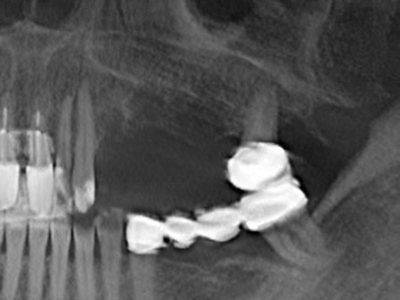

Si es preciso realizar intervenciones quirúrgicas en las que el hueso está en contacto directo con estructuras sensibles, como son los vasos sanguíneos o los nervios, los instrumentos rotativos presentan un enorme potencial de provocar lesiones iatrogénicas. Así, precisamente en la representación de nervios después de una lesión iatrogénica, o en el transcurso de la lateralización de un nervio para resecciones, reconstrucciones o incorporación de implantes, los equipos piezoeléctricos pueden resultar muy útiles para preparar la tapa ósea y retirar las partes de tejido duro cercanas al nervio (fig. 17-20). Por lo general, un ligero contacto del cordón nervioso con el inserto piezoeléctrico no tiene consecuencia alguna; ahora bien, un procedimiento poco cuidadoso con movimientos tipo sierra o piezas de trabajo sobre la base ósea aún existente puede provocar lesiones nerviosas temporales o incluso permanentes. Con todo, el riesgo de sufrir una lesión de este tipo se considera significativamente inferior que en los casos en los que se utilizan sierras y fresas (Pereira, Gealh et al. 2014).